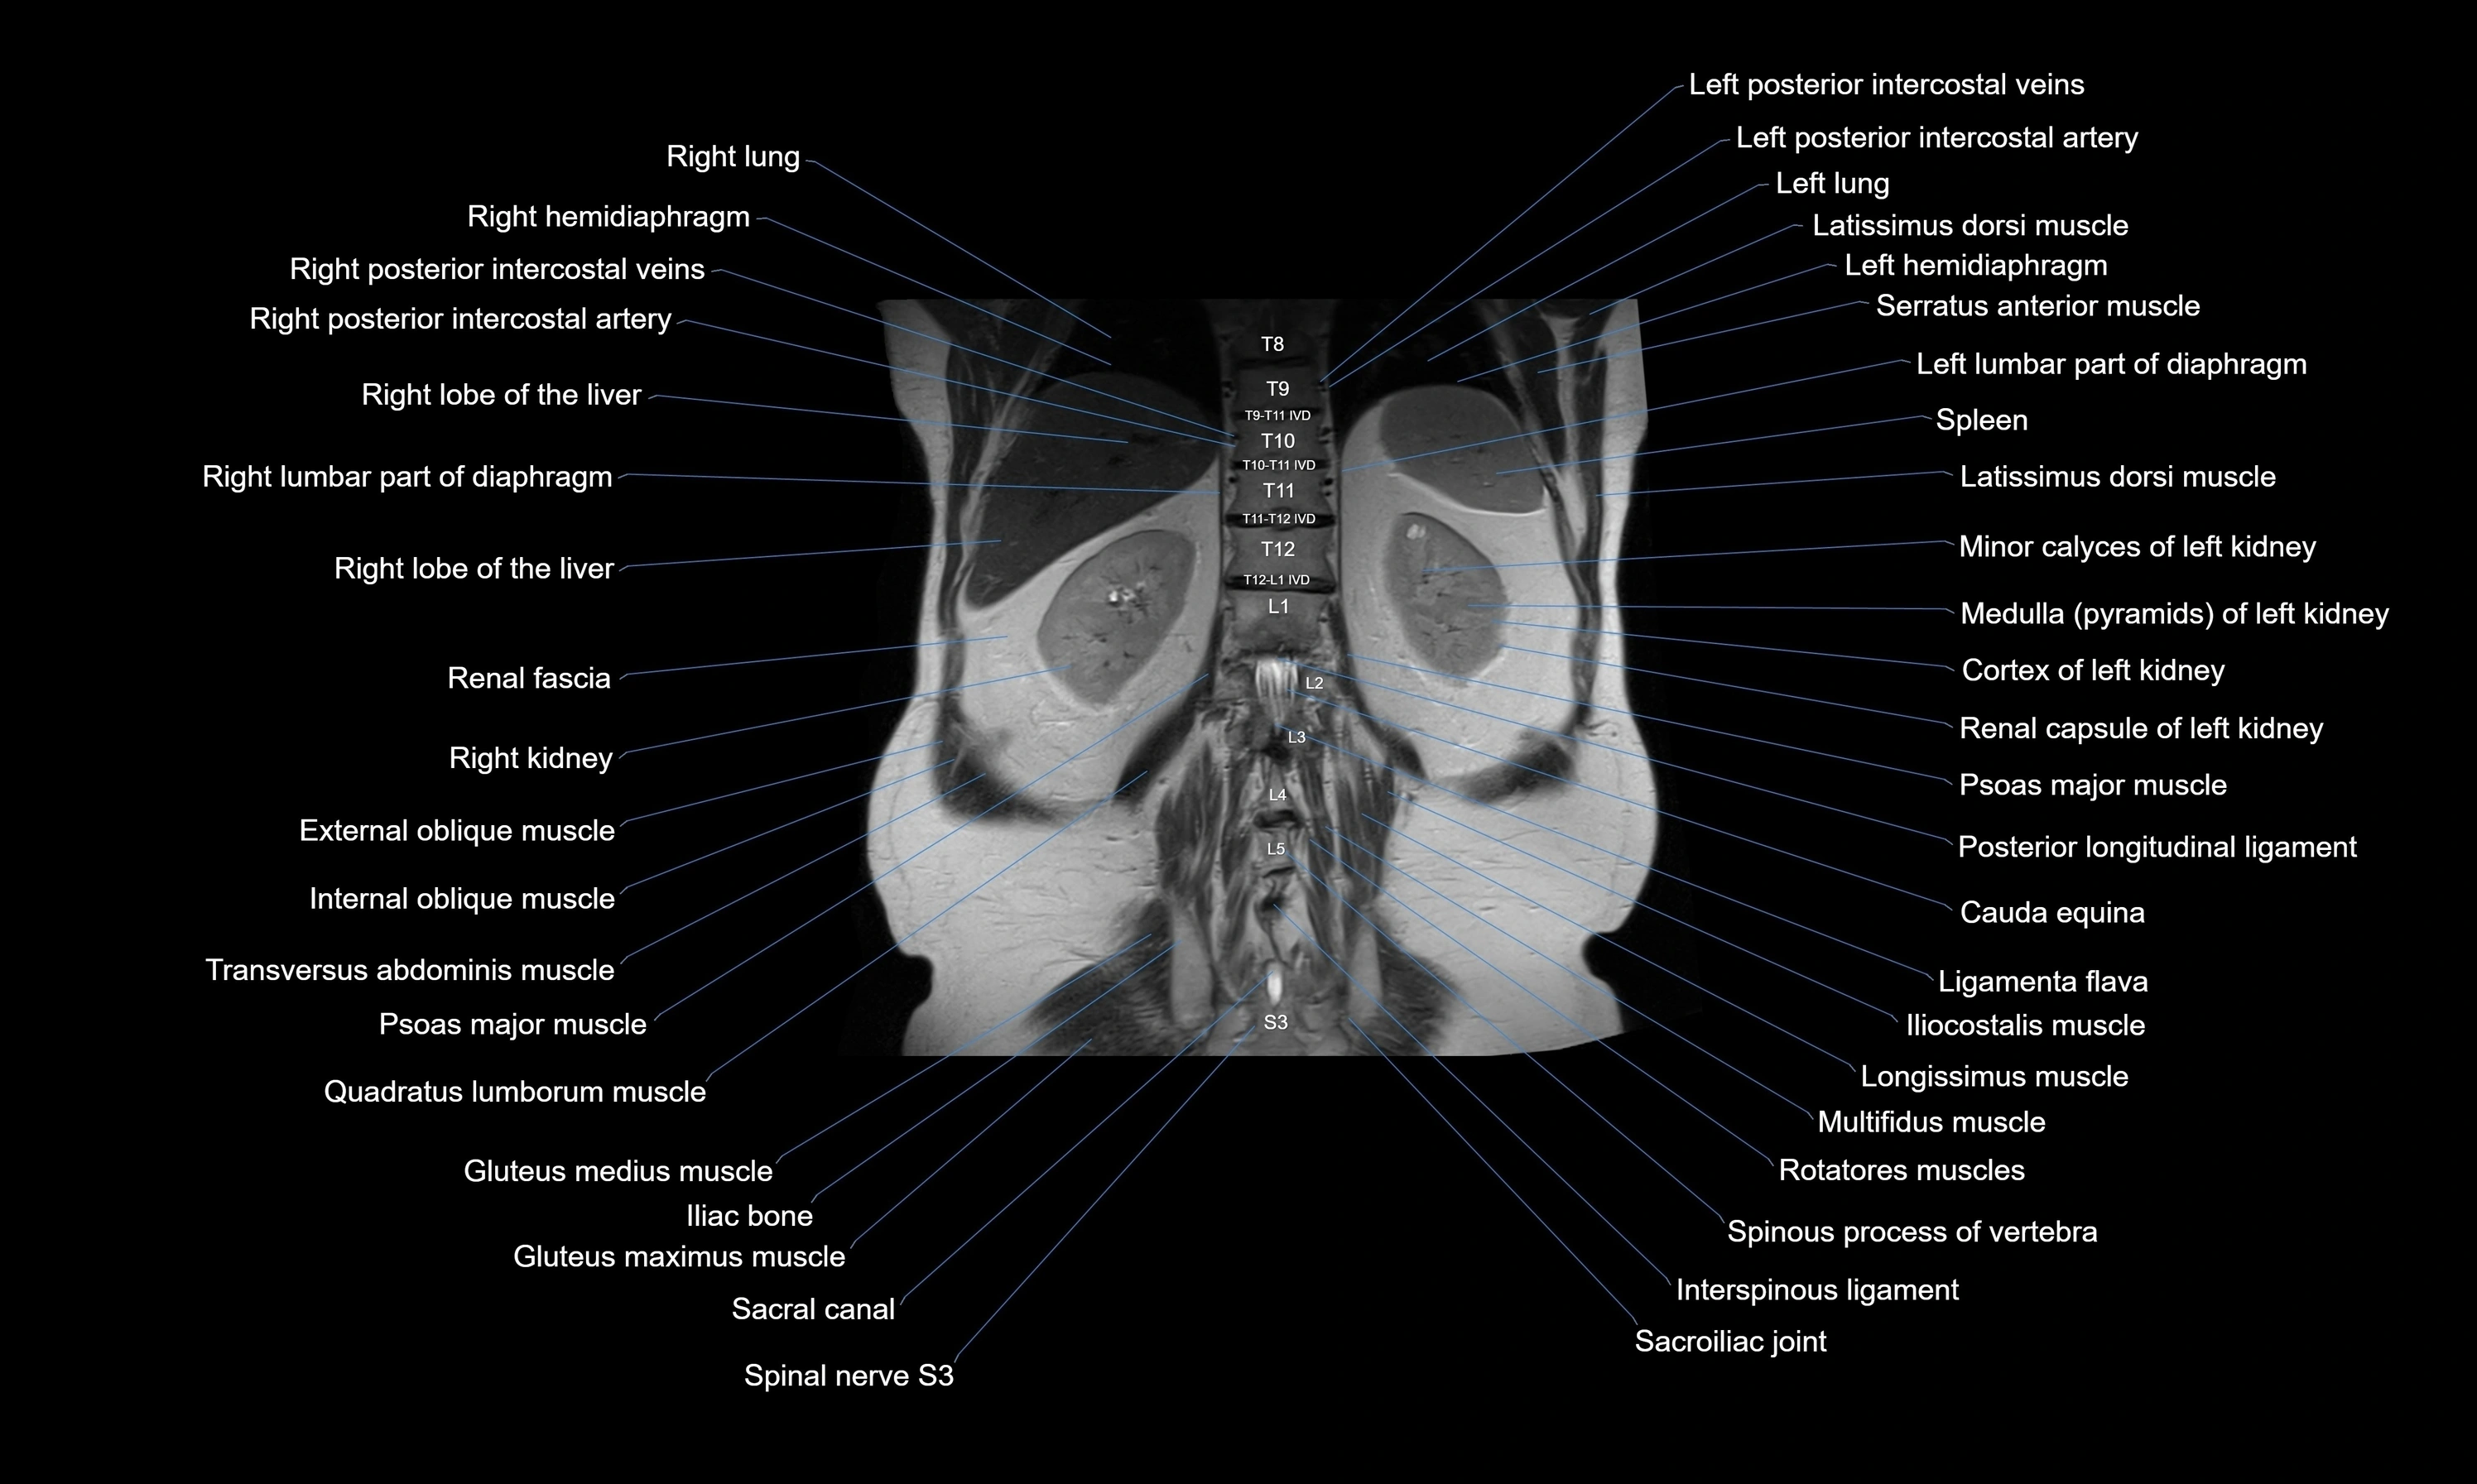

- Cauda equina

- Kidney cortex (Renal cortex)

- Left kidney

- Renal fascia

- Renal medulla

- Right kidney

- Rotatores lumborum muscles

- Rotatores muscle

- Spinal nerve L1

- Spinal nerve S3

- Spleen